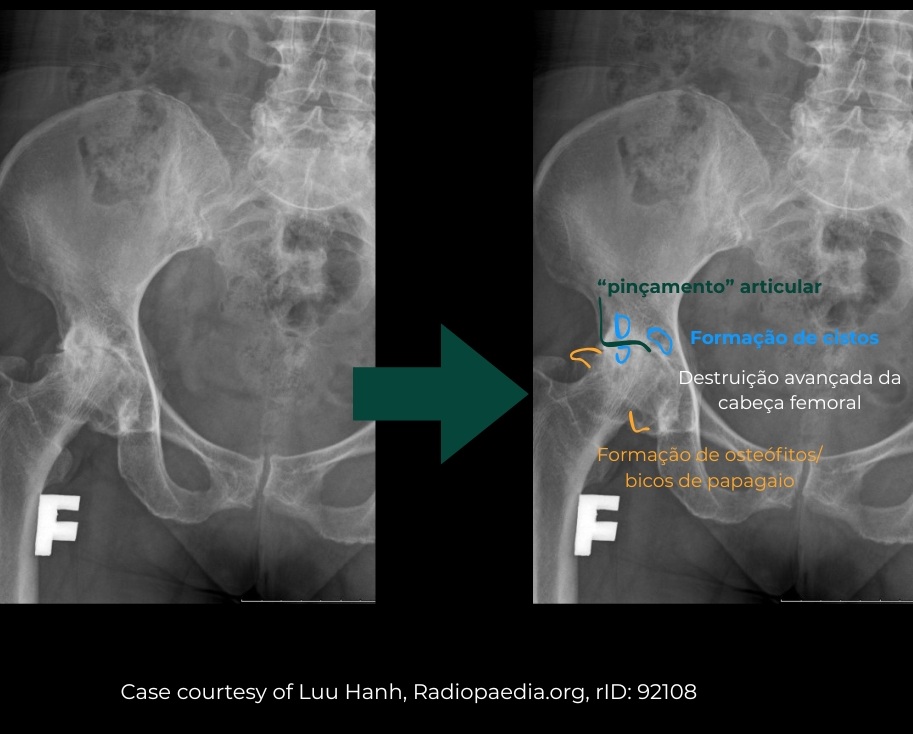

Radiografia do quadril com achados típicos de osteoartrite: Ao lado direito observa-se redução do espaço articular, esclerose óssea, formação de osteófitos e alterações no contorno da cabeça do fêmur e do acetábulo, compatíveis com desgaste da articulação.

A radiografia permite avaliar de forma clara:

• redução do espaço articular;

• presença de osteófitos;

• esclerose óssea;

• alterações no formato da cabeça do fêmur e do acetábulo